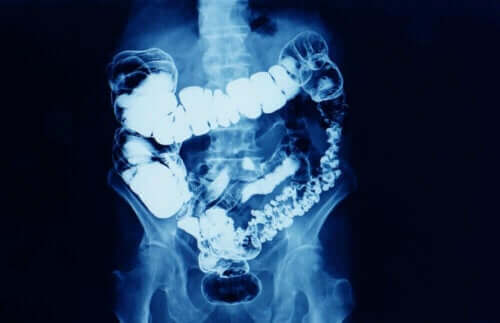

Hvad er forstoppelse?

Generelt er forstoppelse, når hyppigheden af tarmbevægelse reduceres. Forstoppelse er et symptom, som betyder, at tarmtransit bliver reduceret af en grund.

Forstoppelse påvirker kvinder mere end mænd, især kvinder i alderen mellem 20 og 35 og efter 60-års alderen.

Afhængig af hvor længe det varer, kan forstoppelse blive klassificeret i to typer:

- Lejlighedsvis: Dette kan være på grund af ændringer i kosten og indtag af vand, mangel på motion, behandling med bestemte lægemidler og stressende situationer.

- Kronisk: For at læger anser det som kronisk, skal det vare mindst tre måneder.

Kronisk forstoppelse kan være relateret til situationer, som minder om dem for lejlighedsvis forstoppelse, men det varer i længere tid. Andre gange er det på grund af fordøjelsesproblemer og bestemte sygodmme.